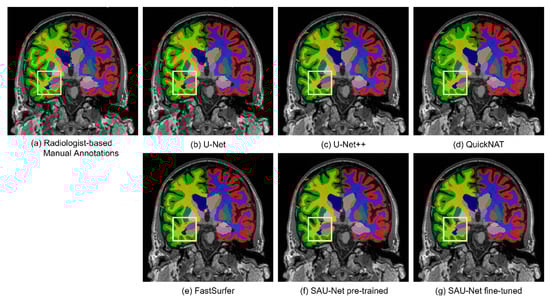

3.1.2. Qualitative Analysis

4.1. Comparison with Deep-Learning Methods

4.4. Segmentation Performance